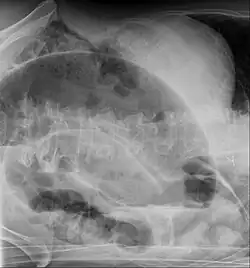

Coffee bean sign in a person with sigmoid volvulus -